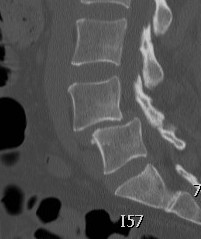

CT

Degeneration of facet